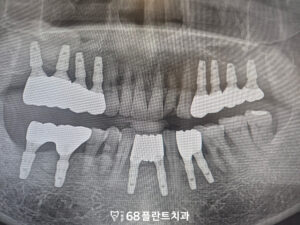

확인해 보니

전체적으로 치주 상태와

치아 건강이 좋지 않았고,

양쪽 위 어금니가 상실된 상태로

오랜 시간이 경과하면서

해당 부위의 잇몸뼈 소실도

함께 진행된 상황이었습니다.

이러한 경우,

임플란트를 식립하여

치아의 기능을 회복하면 되지만

치아의 상실된 시기가 길었다보니

잇몸뼈가 많이 소실되어

식립할 공간이 부족했습니다.

특히 위쪽 어금니 부위에는

상악동이라 불리는 공기 공간이 위치해 있어,

잇몸뼈가 감소할 경우

임플란트를 바로 식립하기가

더욱 어려워질 수 있습니다.